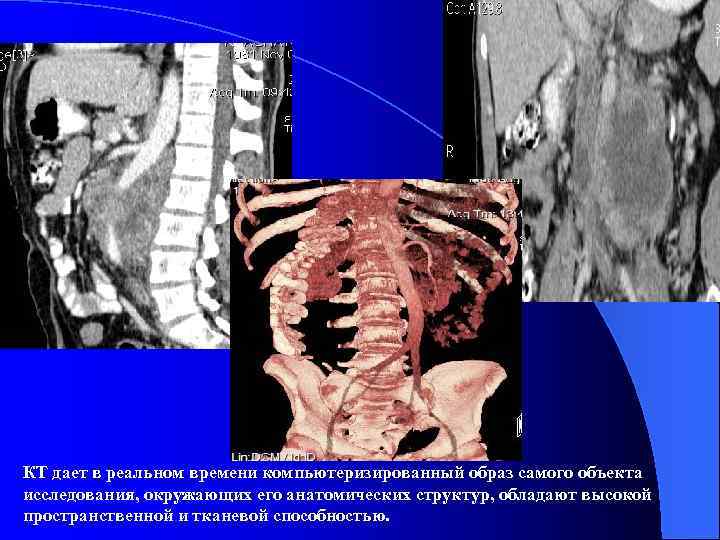

Компьютерная томография SOMATOM EMOTION 6 (SIEMENS) Мультисрезовый рентгеновский компьютерный томограф с длительностью спирали до 100 с, возможностью субмиллиметрового сбора данных с толщиной среза 0, 5 мм и скоростью вращения трубки 0, 6 с за один оборот. • Разработанная конфигурация системы обеспечивает отличное качество изображений при минимально возможной лучевой нагрузке на пациента. • Позволяет выполнять весь спектр рутинных исследований. • Программа CARE Vision (КТ – флюороскопия) позволяет проводить интервенционные вмешательства под контролем КТ сканера, такие как биопсия, дренирование и др. в реальном масштабе времени. • Выполнять ангиографические исследования, количественную оценку васкулярных нарушений. • Аппарат оснащен средствами трехмерной постпроцессорной обработки изображений для решения диагностических задач.

КТ дает в реальном времени компьютеризированный образ самого объекта исследования, окружающих его анатомических структур, обладают высокой пространственной и тканевой способностью.